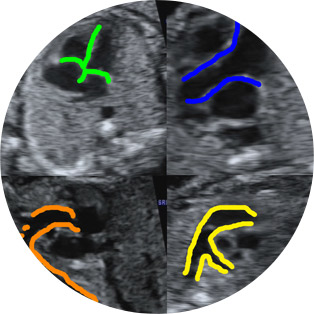

Οι βασικές τομές που λαμβάνονται είναι η τομή των 4 κοιλοτήτων της καρδιάς, όπου ανακαλύπτεται το 60% των βλαβών της, η τομή εξόδου της αορτής και της πνευμονικής αρτηρίας, καθώς και η τομή των 3 αγγείων όπου γίνεται ενδελεχής έλεγχος των μεγάλων αγγείων και των συνδέσεων μεταξύ τους. Σε τυχόν υπόνοιες βλαβών, λαμβάνονται επιπλέον τομές ή ζητείται ειδικός υπερηχο-εμβρυο-καρδιολογικός έλεγχος του εμβρύου.